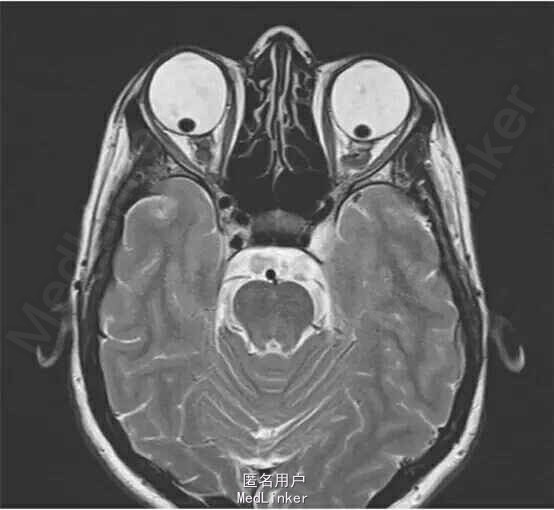

眼科查体:双眼巩膜呈蓝色,双眼视力明显下降,右眼视力为 0.25,左眼为 0.05,双眼眼压正常;瞳孔散大后裂隙灯检查发现双眼晶状体脱位入玻璃体腔,眼底检查发现存在视网膜变性,但是未见视网膜撕裂及视网膜脱离的任何迹象。 患者出现无法解释的听力下降而予以头颅 MRI 扫描,在眼眶的 MRI 扫描 T2 影像图片(图 1)中可见双眼晶状体向后异位入玻璃体腔。 图 1:患者头颅 MRI 扫描中经眼眶层面的 T2 影像